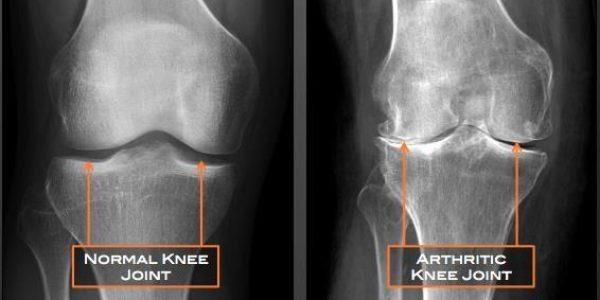

Knee Osteoarthritis

Osteoarthritis of the knee happens when cartilage in your knee joint breaks down.